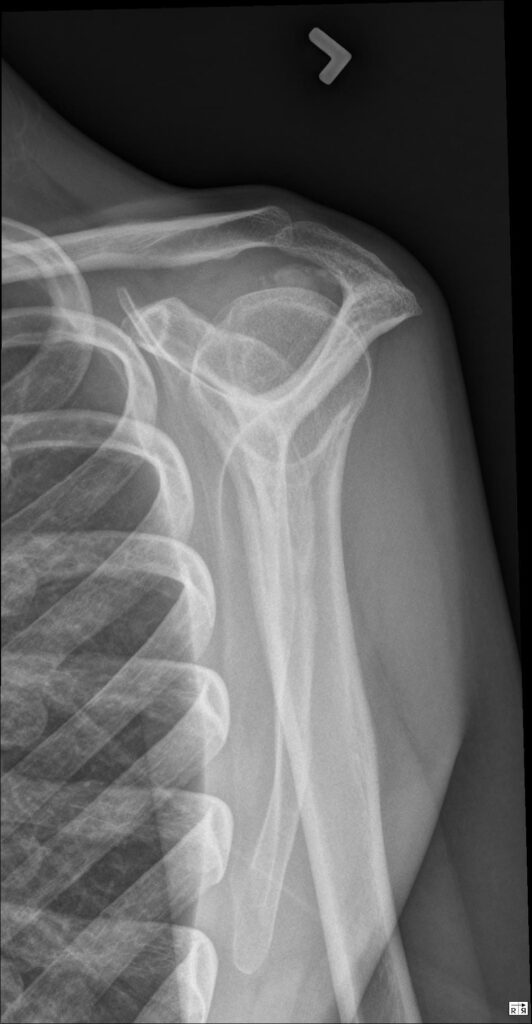

Posterior dislocation of the shoulder occurs when the head of the humerus is displaced backward out of the glenoid fossa. This displacement typically results from powerful internal rotation forces and may be associated with soft tissue or bony injuries around the shoulder joint.

- Flattened anterior shoulder with posterior fullness.